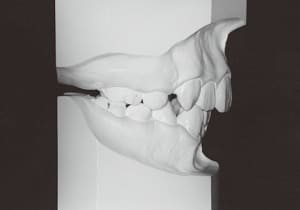

The Class II condition is pronounced, with a significant overjet of 12.5 mm(3). Although the teeth size are large, crowding is relatively mild. The maxillofacial structure has good depth and a robust bone framework(5). The mandible itself is solid , robust gonial angle, but there is significant anterior-posterior displacement relative to the maxilla(ANB 10.0°). While there is no confirmed history of thumb-sucking or similar habits, the lower lip is already pushing up against the maxillary incisors. The cause of this condition is unknown.

The first phase of treatment involved extracting the left and right maxillary deciduous canines. The space created was used to forcibly retract the four anterior teeth, thereby aiming to improve lip closure function (6–9, 11). Morphological changes suggest that lip function differed before and after treatment (6, 9). Subsequently, the first premolars erupted, but extraction is planned to secure space for canine eruption (10). A Class II molar relationship remains, but the significant overjet has improved (11).

In the maxilla, insufficient space for canine eruption was inevitable, necessitating extraction as part of the treatment plan. The maxillary first premolars on both sides were extracted during routine observation to create space for canine eruption (14). Eventually, the canines erupted and settled into relatively favorable positions (15,19,20). In the mandibular dentition, crowding was also present, leading to extraction of the mandibular first premolars on both sides. Treatment with full bracket was then initiated (17).